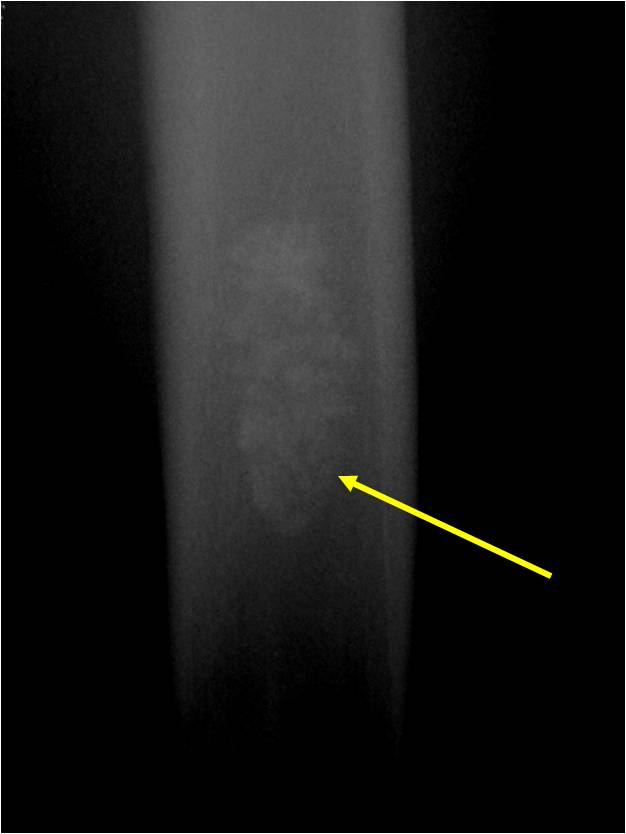

- Localized, radiolucent defect usually with punctate calcifications

- Calcifications are typical but not always present

- Matrix may demonstrate various degrees of calcification

Plain X-Ray:

- Geographic lytic lesion

- Central often metaphyseal in long bones

- Expansile remodeling with thinned cortex

- Chondroid matrix with calcifications in majority of tumors

- Approximately 20% have limited or no calcifications